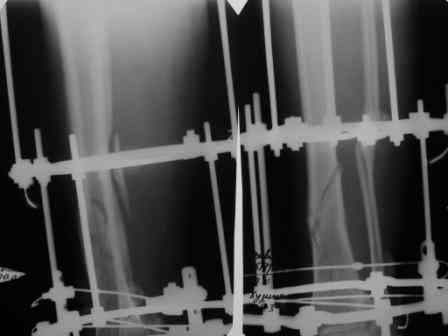

Сегодня мною была осмотрена больная, которой я выполнил накостный остеосинтез около четырех месяцев назад по поводу фрагментарного перелома бедра на уровне средней трети и межвертельной зоны.

Перелом синтезированный DHS сросся, а вот на уровне средней трети - нет. И, похоже, есть нехорошая тенденция к резорбции.

Больную беспокоит умеренный отек голени и стопы. Нагрузку на конечность не разрешаю, ибо недавно у молодого пациента при аналогичном переломе и остеосинтезе произошел перелом пластины на уровне нижней трети бедра...

Обращаясь к Александру Николаевичу, хочется узнать о целесообразности удаления металлоконструкции и интрамедуллярном штифтовании у них в институте у данной больной. Если есть резон, то нужно обговорить финансовую сторону вопроса ...

По поводу моей больной с фрагментарным переломом бедра ...

Больная 47 лет, поступила в отделение после автодорожной травмы от 08 июля сего года с DS: ЗЧМТ, СГМ. Закр. чрезвертельный перелом и перелом с/3 левого бедра со смещением. Ушиб и рваная рана левого коленного сустава. Соп.: Хр. железодефицитная анемия. (Гемоглобин при поступлении 71 г/л). 08 июля - ПХО ран колена.

11 июля остеосинтез бедра DHS + LC DCP.

Я выкладывал на Форум этот случай, где высказывались опасения, что не исключается варусная дислокация межвертельного перелома на фиксаторе из-за малой длины Screw ... вроде пронесло ... перелом сросся. Но маленькая

победа в отдельной битве, все же не принесла победы в целом... Остается неопорная конечность, ограничение движений в коленном суставе 180 - 150 град., отечность голени и стопы, по-видимому, из-за сосудистой недостаточности, гипотрофии

мышц ноги ... При выписке из стационара Hb - 97 г/л (препараты железа, рибофлавины).

По настоящий момент наблюдается амбулаторно. Передвигается с опорой на костыли. Горит желанием встать "на крыло" ... Ждем Вашего решения. Может быть нужны дополнительные снимки?

Возьметесь ли за этот случай? Ну, и самое главное - стоимость лечения ...

По поводу фрагментарного перелома бедра на уровне средней трети и межвертельной зоны, мы рекомендуем ретроградное введение интрамедуллярного штифта для диафизарных переломов и фиксацию чрезвертельного перелома DHS, но имплант применяем с углом, меньшим 130 градусов.

DHS с углом более 135 градусов при введенном шеечном компоненте ниже уровня малого вертела создает опасность стрессового перелома из-за

слабости латерального кортекса.

Для предотвращения межимплантных стрессовых зон, длина штифта доводится почти до малого вертеля, а у DHS не обязательно, чтобы все шурупы были двухкортикальными, нижние могут быть уникортикальными.

Замена имплантов на интрамедуллярный решила бы проблему со сращением.